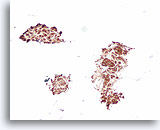

Afbeelding 20

Benigne, lymfocytische thyroïditis, schildklier FNA, celblok.

Deze afbeelding van de patiënt in afbeelding 19 toont een dicht lymfocytisch infiltraat met aangrenzende afgeplatte microfollikels met hurthlecelveranderingen.

20X

Afbeelding 20

Benigne, lymfocytische thyroïditis, schildklier FNA, celblok.

Deze afbeelding van de patiënt in afbeelding 19 toont een dicht lymfocytisch infiltraat met aangrenzende afgeplatte microfollikels met hurthlecelveranderingen.

20X